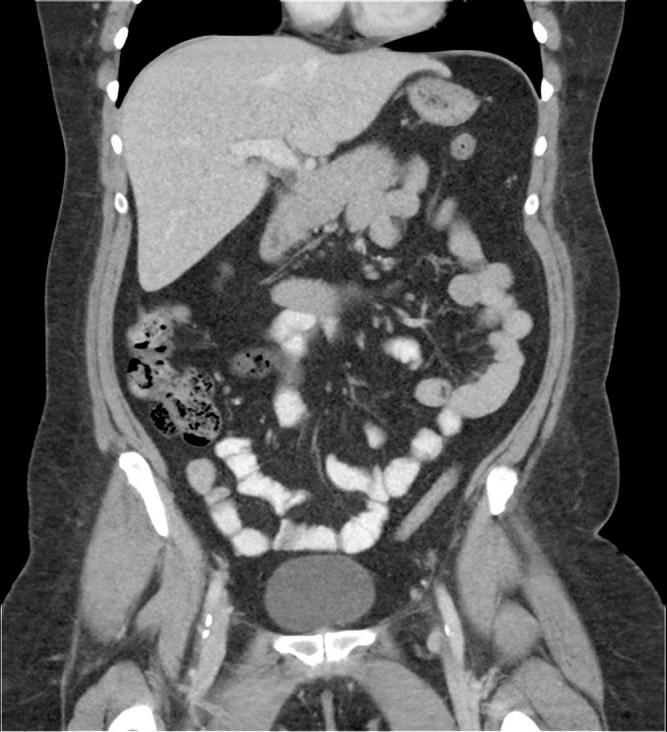

Intestinal angioedema is a rare side effect of angiotensin-converting enzyme inhibitors. We present a 41-year-old woman with sporadic right lower quadrant abdominal pain and diarrhea with multiple computed tomography scans demonstrating enteritis. Suspicion turned to angiotensin-converting enzyme inhibitor use as the cause for the patient's illness after an extensive negative evaluation including labs, stool studies, endoscopies, and capsule endoscopy. Weeks after stopping the medication, the patient's symptoms improved and repeat computed tomography showed a resolution of the previously seen findings of enteritis. This case illustrates the importance of a good medication review to make appropriate clinical decisions and diagnoses.

肠道血管性水肿是血管紧张素转换酶抑制剂的一种罕见副作用。我们报告一名41岁女性,有散发性右下腹腹痛和腹泻,多次计算机断层扫描显示为肠炎。在进行包括实验室检查、粪便研究、内镜检查和胶囊内镜检查在内的广泛阴性评估后,怀疑病因是血管紧张素转换酶抑制剂的使用。停药数周后,患者症状改善,重复计算机断层扫描显示先前所见的肠炎表现已消退。该病例说明了进行良好的用药回顾以做出适当临床决策和诊断的重要性。